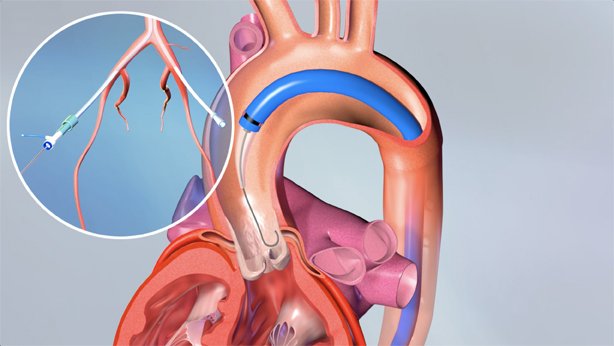

EnCompass F2 Device for cerebral embolic protection system in TAVR procedures

EnCompass Technologies

EnCompass’ F2 filter has pores small enough to block most emboli to the brain while preserving blood flow. During the TAVR procedure, 360-degree wall apposition of the filter in the aortic arch prevents migration. The filter, attached to a self-expanding, nitinol stent, is easy to insert, deploy and retrieve, according to the company. Copyright ©2021 KO Studios.